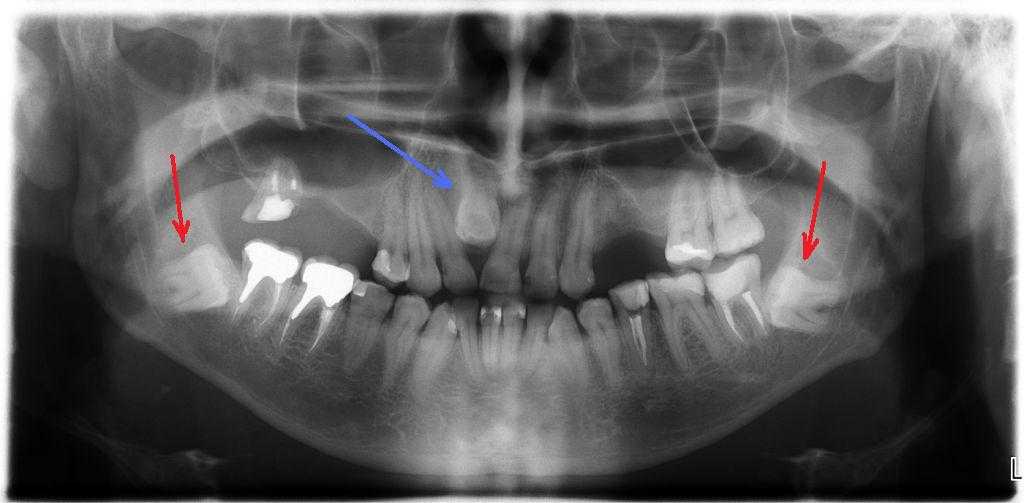

Второй ряд зубов — также черта, присущая нашим далеким предкам. К примеру, у акулы их несколько рядов. Это необходимо хищникам для эффективного захвата и удержания добычи. Существует мнение, что атавизмом можно считать и микроцефалию. Это генетическое заболевание, которое проявляется в уменьшении размеров головного мозга и черепа. При этом все остальные пропорции тела остаются в норме. Это влечет за собой умственную отсталость.